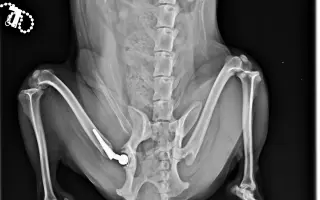

Akutní operace kyčle pro Charlieho: pomozte mu opět běhat bez bolesti